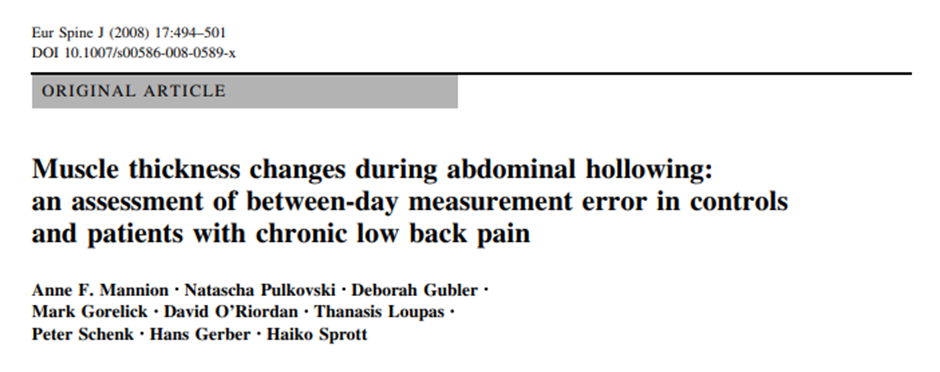

Mannion et al. (2008, 2010)에 2008년도의 연구 논문에 따르면 복횡근의 우선적인

활성화비율( TrA preferential activation ratio)의 차이로 요통의 원인과 기전을 설명하기에

임상적 으로 사용하기에는 지나치게 모호하다고 지적하고있습니다.

요통환자와 대조군환자의 복횡근의 두께 측정표 및 지수 중에서 복횡근의 Abdominal

Hollowing동안의 우선적인 활성화 비율(TrA preferential activation ratio)과 복횡근

근육의 두께차이에 따른 요통유무의 낮은 신뢰성 때문에 임상에서의 사용에 의문이

제기된다고 언급하고있습니다.

외측 복벽두께의 측정값을 신뢰할 수 있습니까?

휴식 시 측면복벽두께의 차이는 증상이 없는 일반인에게도 빈번하게 나타납니다.

그러므로 요통환 자들에게서 나타나는 복부근육두께의 차이는 임상적으로 관련이

없다고합니다.

앞서 언급한 2008년도 요통 환자 그룹(Mannion et al.,2008) 와 무증상 집단 그룹

연구에서의 복벽두께의 차이 범위는 11%-26%으로 높은 표준편차를 보였습니다.

그러므로 임상에서 요통 환자들의 측면 복근 두께의 비대칭을 확대 해석하는 것을

주의해야 한다고 권고하고있습니다.

Mannion et al은 체질량지수(BMI)가 절대적인 복부근육 두께의 예측변수라는 것을

발견했고,휴식 시나 Abdominal Hollowing 시 모든 근육에 있어 30-44%의 변동을

보였습니다.

즉 요통의 유무와는 상관없이 BMI는 지방량에 따른 근육두께의 차이로 복횡근의

우선적인 수축비율에 20 -30%의 변동을 만들수 있습니다.

그러므로 환자에서 보이는 복횡근또는 복부근육의 두께의 비대칭을 판단함에 있어

정상인에게서도 일반적으로 볼수 있는 현상이기 때문에 주의를 기울여야 합니다.